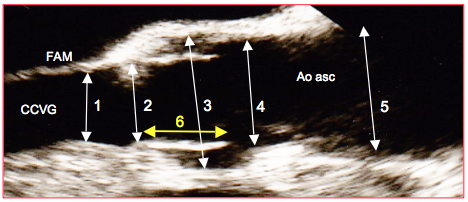

Figure 27.96 : Dimensions de la racine de l’aorte: diamètres en long axe 120° (ETO). 1 : chambre de chasse du VG. 2 : anneau aortique. 3 : sinus de Valsalva. 4 : jonction sino-tubulaire. 5 : aorte ascendante. 6 : hauteur de la cuspide droite (jaune). Ces diamètres se mesurent en systole. Le diamètre de l’aorte ascendante se mesure en diastole; une manière claire de s'accorder sur le niveau de cette dernière mesure est de la faire au croisement de l’artère pulmonaire droite (non visible sur l’image).